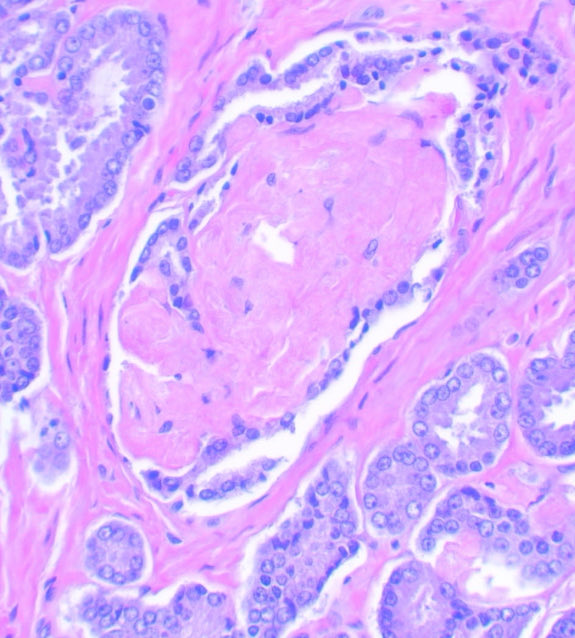

A bona fide GP 3 prostatic carcinoma: well formed discrete 👌🏽 See why you shouldn’t grade PNI? 🤓 #GUpath #PathX #Pathology #PathTwitter